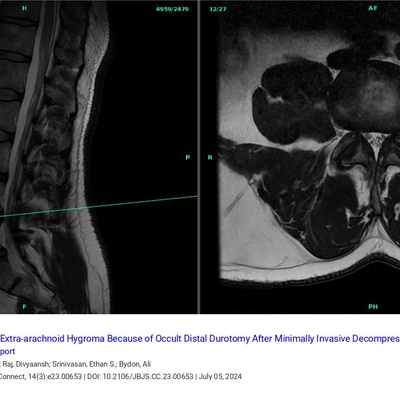

J Bone & Joint Surg